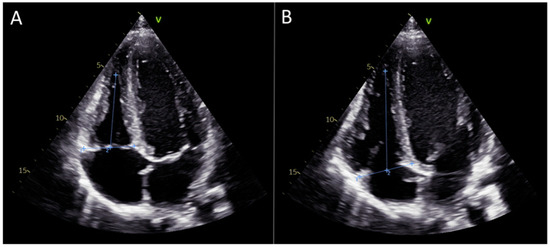

Right Ventricular Functional Improvement After Lung Transplantation and Adjunctive Pulmonary Rehabilitation: An Echocardiographic Analysis

by Meltem Altınsoy, Deniz Çelik, Fadime Bozduman Habip, Pınar Ergün, Hasret Gizem Kurt, Sertan Bulut, Hüsnü Baykal and Yusuf Taha Güllü

Background: Right ventricular (RV) dysfunction is common in advanced lung disease due to chronic pressure overload and altered pulmonary vascular mechanics. Lung transplantation (LTx) reduces RV afterload, and pulmonary rehabilitation (PR) may further enhance functional recovery. However, the combined effects of LTx and [...] Read more.

Background: Right ventricular (RV) dysfunction is common in advanced lung disease due to chronic pressure overload and altered pulmonary vascular mechanics. Lung transplantation (LTx) reduces RV afterload, and pulmonary rehabilitation (PR) may further enhance functional recovery. However, the combined effects of LTx and structured PR on RV myocardial deformation—particularly using speckle-tracking echocardiography (STE)—remain insufficiently characterized. Methods: This single-arm pre–post study included 20 bilateral lung transplant recipients who completed an 8-week, twice-weekly supervised outpatient PR program. Echocardiographic evaluation—including 2D measurements, M-mode, tissue Doppler imaging (TDI), and STE-derived strain parameters—was performed immediately post-discharge (baseline) and after PR. RV global longitudinal strain (RVGLS) and RV free-wall longitudinal strain (RVFWS) served as primary functional outcomes. Results: Improvements were observed in RV myocardial deformation after PR. RVGLS improved from a median of 15.52% to 16.64% (p = 0.004), and RVFWS increased from 15.82% to 17.10% (p = 0.001). RV mid-cavity diameter decreased significantly (p = 0.042), reflecting favorably altered RV geometry. Conventional parameters—including TAPSE, S′ velocity, RVEDA, and FAC—showed no statistically significant changes. These findings indicate that STE parameters are more sensitive than traditional indices for detecting early RV remodeling in the post-transplant period. Conclusions: Lung transplantation combined with a structured PR program was associated with early improvements in RV deformation indices measurable by STE, even when traditional echocardiographic indices remained within normal limits. STE may therefore serve as a sensitive tool for monitoring subclinical RV recovery after LTx and for assessing the additive benefits of PR. Full article

Figure 1